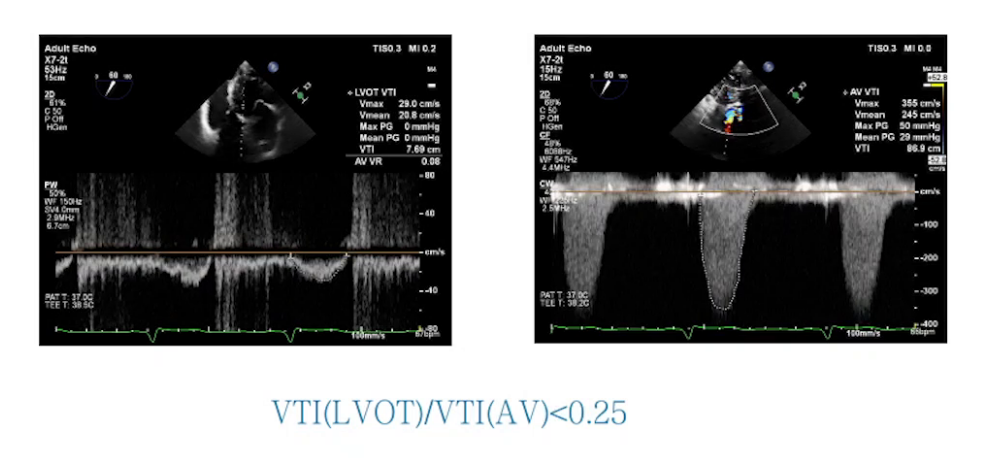

2.麻醉维持:采用环泊酚复合右美托咪定、舒芬太尼和顺阿曲库铵持续泵注维持麻醉。术前TTE检查进一步明确主动脉瓣及二尖瓣病变,同时通过超声指标判断主动脉瓣狭窄程度。Swan-Ganz导管数据显示患者心功能差,但混合静脉血氧饱和度表明全身组织灌注尚可。

超声心动图:LVEF值低,左室流出道内径增大,主动脉瓣存在狭窄及反流,二尖瓣关闭不全,外院冠脉CAG提示前降支供血区域缺血,右冠远端100%闭塞。